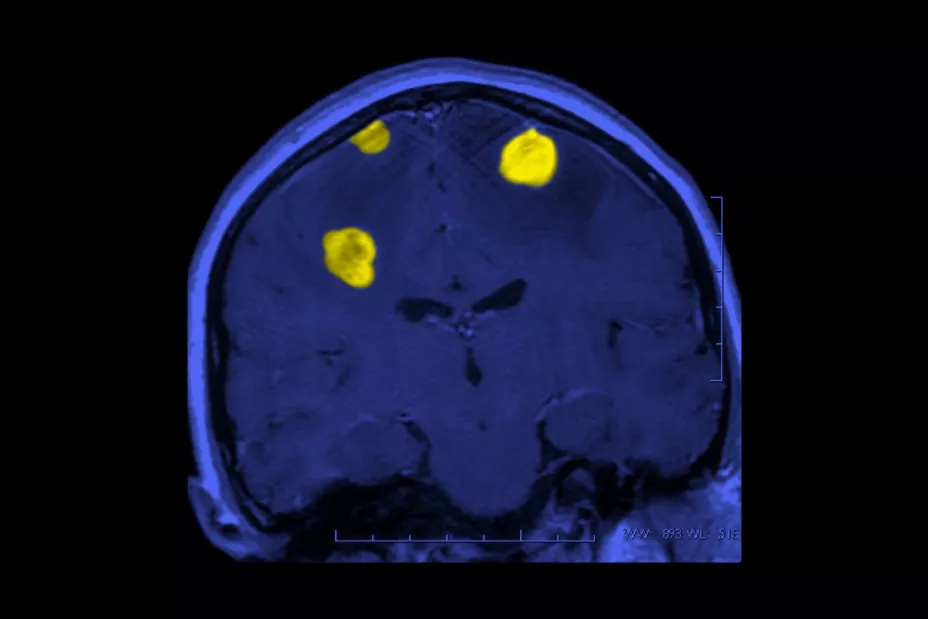

Dependiendo de los resultados, el paciente puede someterse a una o más pruebas mediante tomografía computarizada (TC), resonancia magnética, tomografía por emisión de positrones (PET) u otros tipos de escáneres cerebrales.